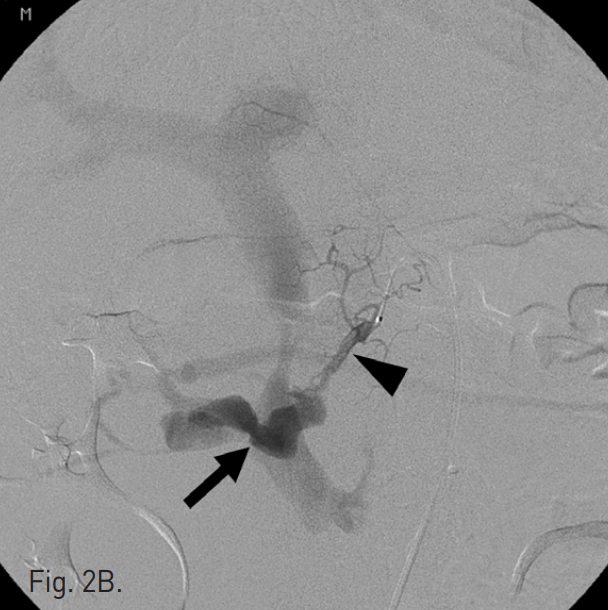

B. Seective angiography of dorsal pancreatic artery (arrow head) shows pseudoaneurysm and arteriovenous fistula to superior mesenteric vein. Por tal vein is visualized erly due to fistulation (arrow).

초음파 및 투시 하에서 우측 대퇴동맥을 천자하고 5F Cobra catheter(Cook, Bloomington, IN, USA)를 이용하여 복강동맥 및 상장간막동맥 조영술을 시행하였다. 복강동맥 조영술에서 dorsal pancreatic artery에서 유출되는 조영제의 누출과 거짓동맥류를 확인하였고 상장간막 정맥으로의 동정맥루를 확인하였다(Fig. 2A, B). Microcatheter(Renegade, Boston Scientific, Natick, MA, USA)를 이용하여 이 거짓동맥류를 선택하였고, 10mm Interlock coil(Boston Scientific, Natick, MA, USA) 6개와, 10mm Nester coil(Cook, Bloomington, IN, USA) 3개를 사용하여 embolization을 시행하였다(Fig. 2C). 이후 남아있는 거짓동맥류와 동정맥루에 대하여 NBCA와 lipiodol mixture(3:1)를 이용하여 색전술을 시행하였다. 시술 후 동맥조영술에서 남아있는 거짓동맥류나 상장간막 정맥으로의 동정맥루는 보이지 않았다(Fig. 2D).